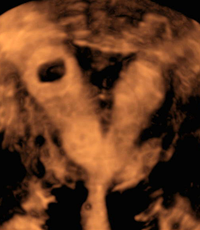

Septated uterus, 3D image.

Septated uterus, pregnancy in left horn, 3D image.

Septated uterus, pregnancy in right horn, 3D image.